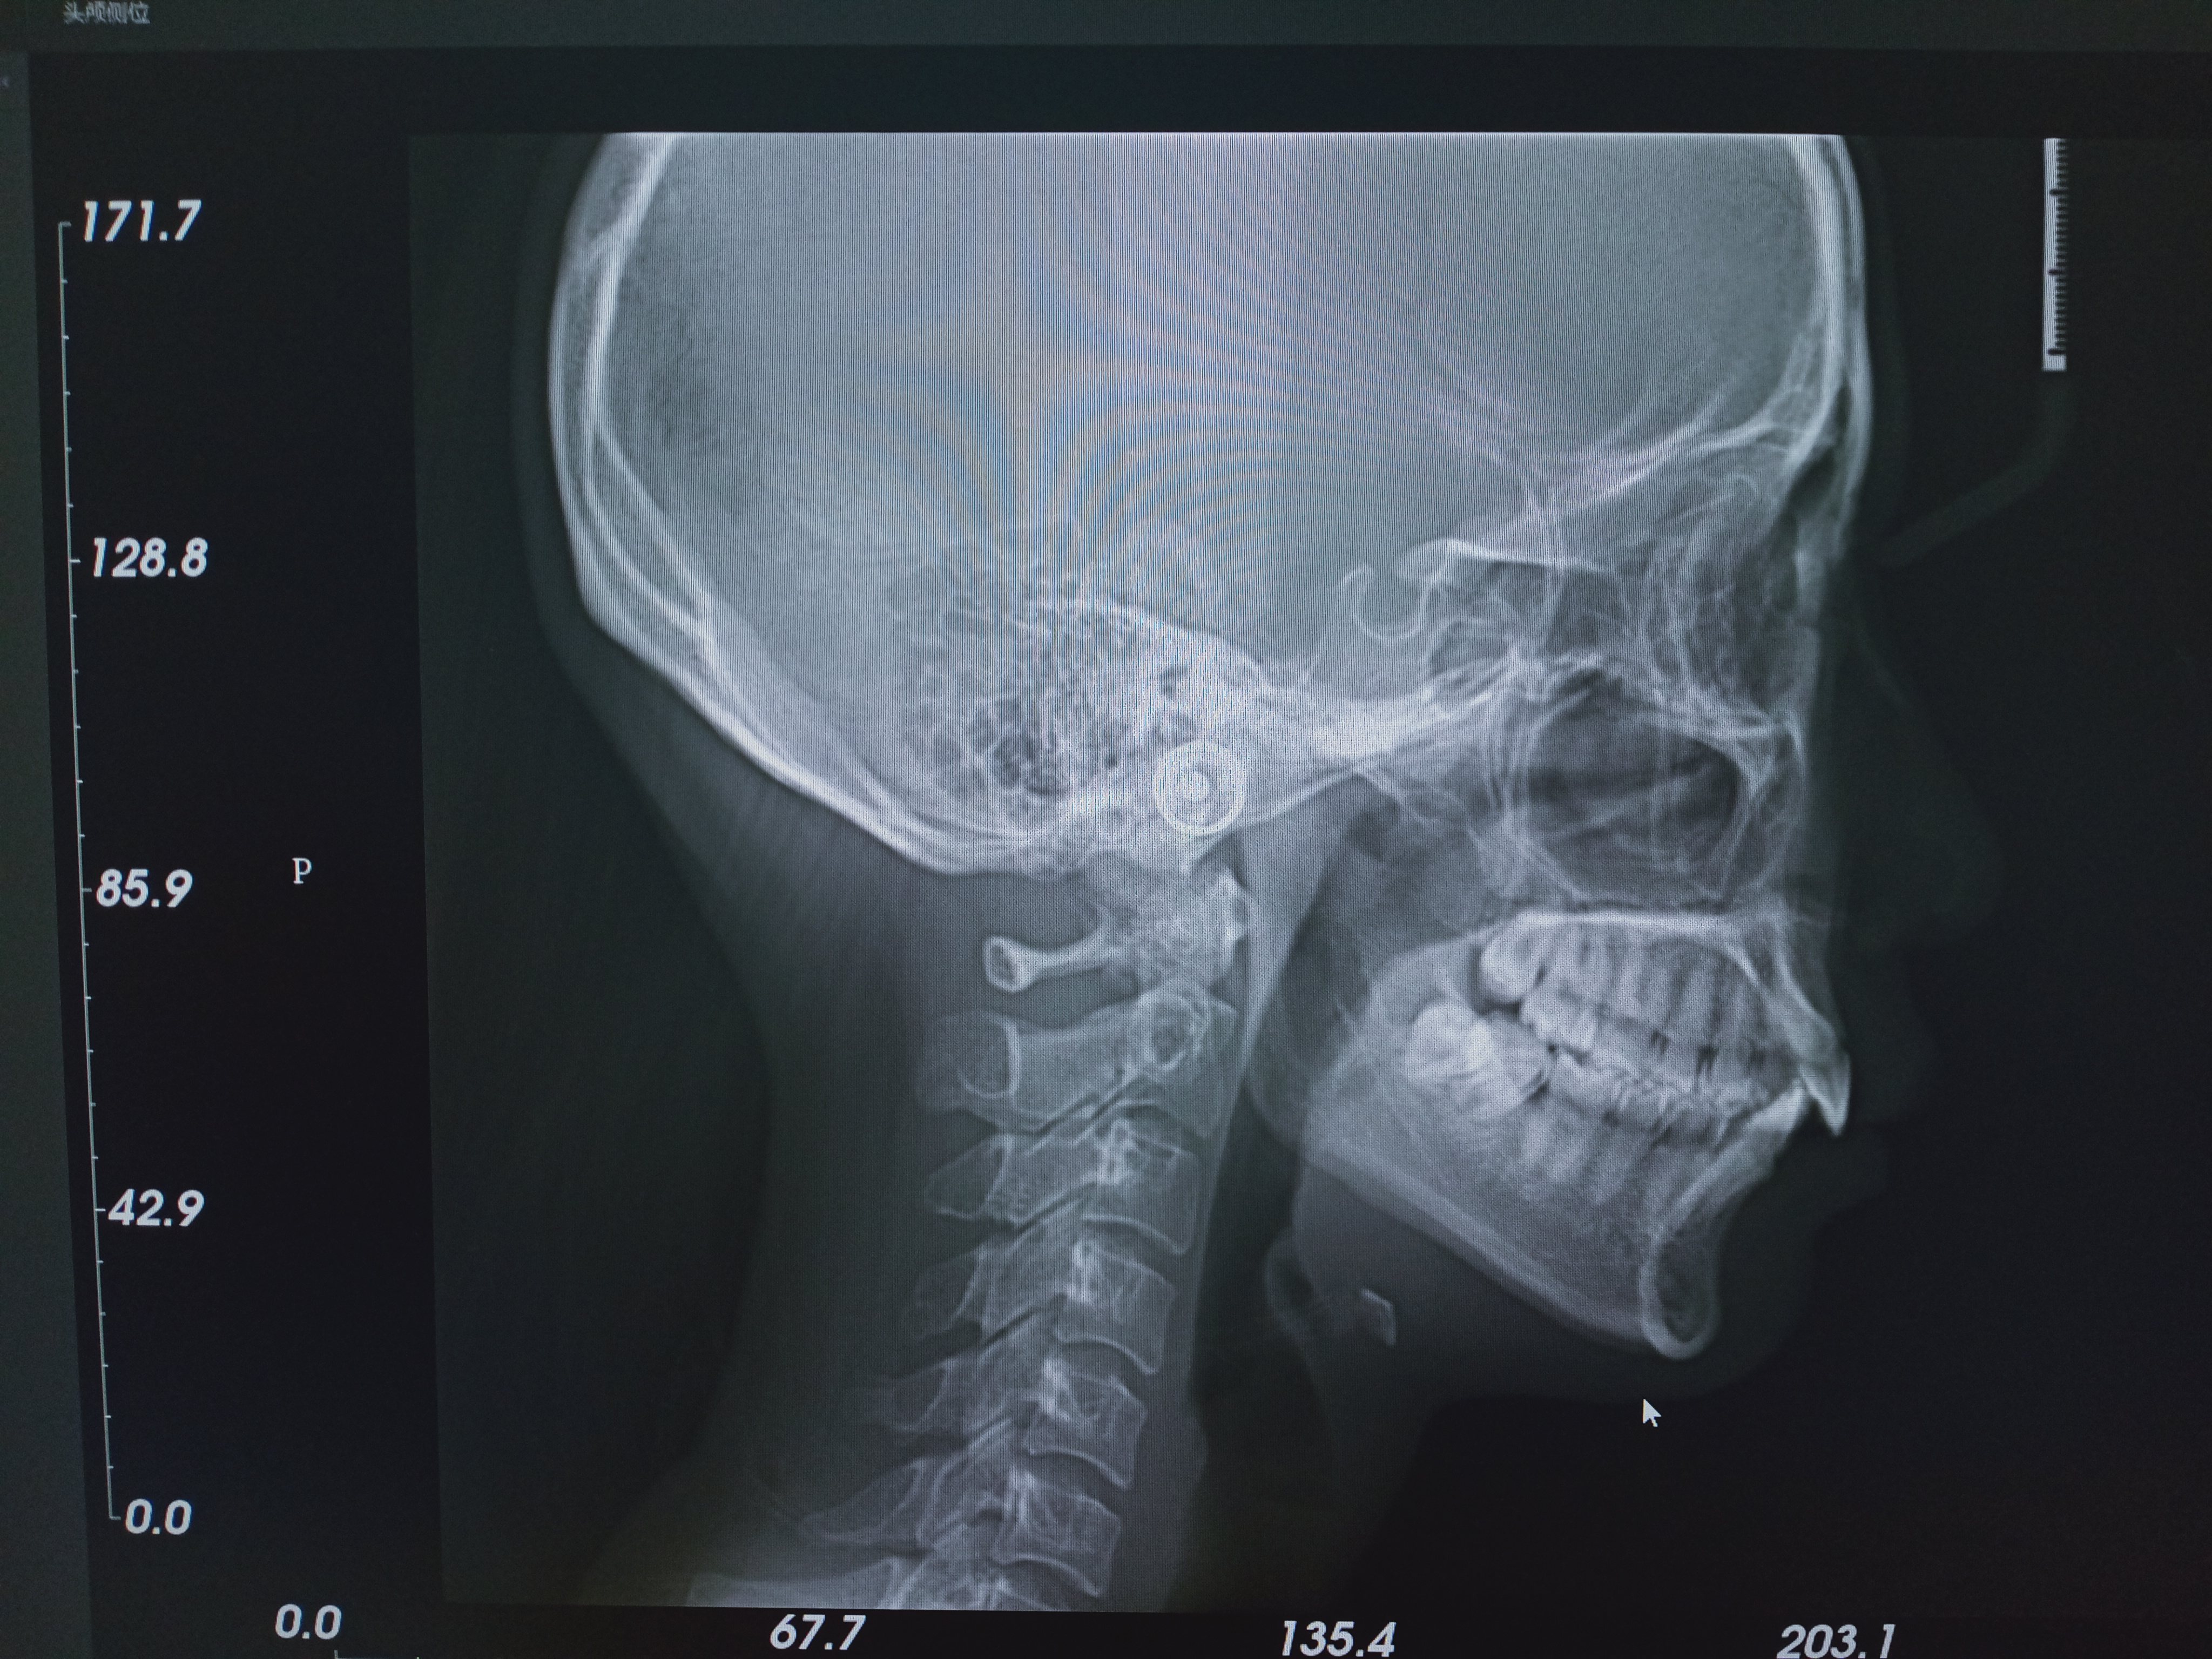

3、头颅侧位片:用于展示颅骨和牙的侧方形态,可清晰具体诊断出各类牙的错颌畸形,口腔正畸医师通过该片测量出重要的参考数据进行一对一的牙矫正方案的设计以便达成更有效的正畸治疗效果。